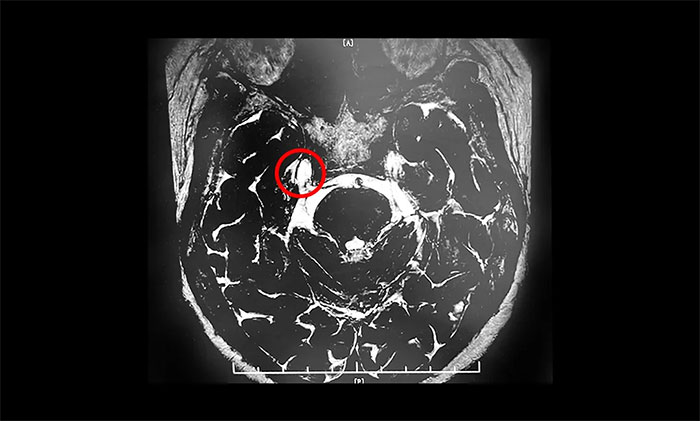

▲ 一位飽受三叉神經(jīng)痛折磨的患者,順利接受微血管減壓手術(shù)治療

微血管減壓術(shù)是現(xiàn)代神經(jīng)外科典型的微創(chuàng)手術(shù)之一,僅通過(guò)患者耳后發(fā)際內(nèi)4-5cm的切口,于顯微鏡下探查三叉神經(jīng)走行區(qū),將所有可能產(chǎn)生壓迫的血管、蛛網(wǎng)膜條索都“松解”開,并將這些血管以Tefflon墊片與神經(jīng)根隔離。一旦責(zé)任血管被隔離,產(chǎn)生刺激的根源就消失了,三叉神經(jīng)核的高興奮性就會(huì)隨之消失,恢復(fù)正常。絕大多數(shù)患者術(shù)后疼痛立即消失,并保留正常的面部感覺和功能,不影響生活質(zhì)量。